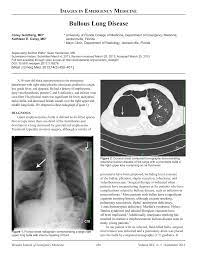

Bullous Lung Disease The Western Journal Of Emergency Medicine